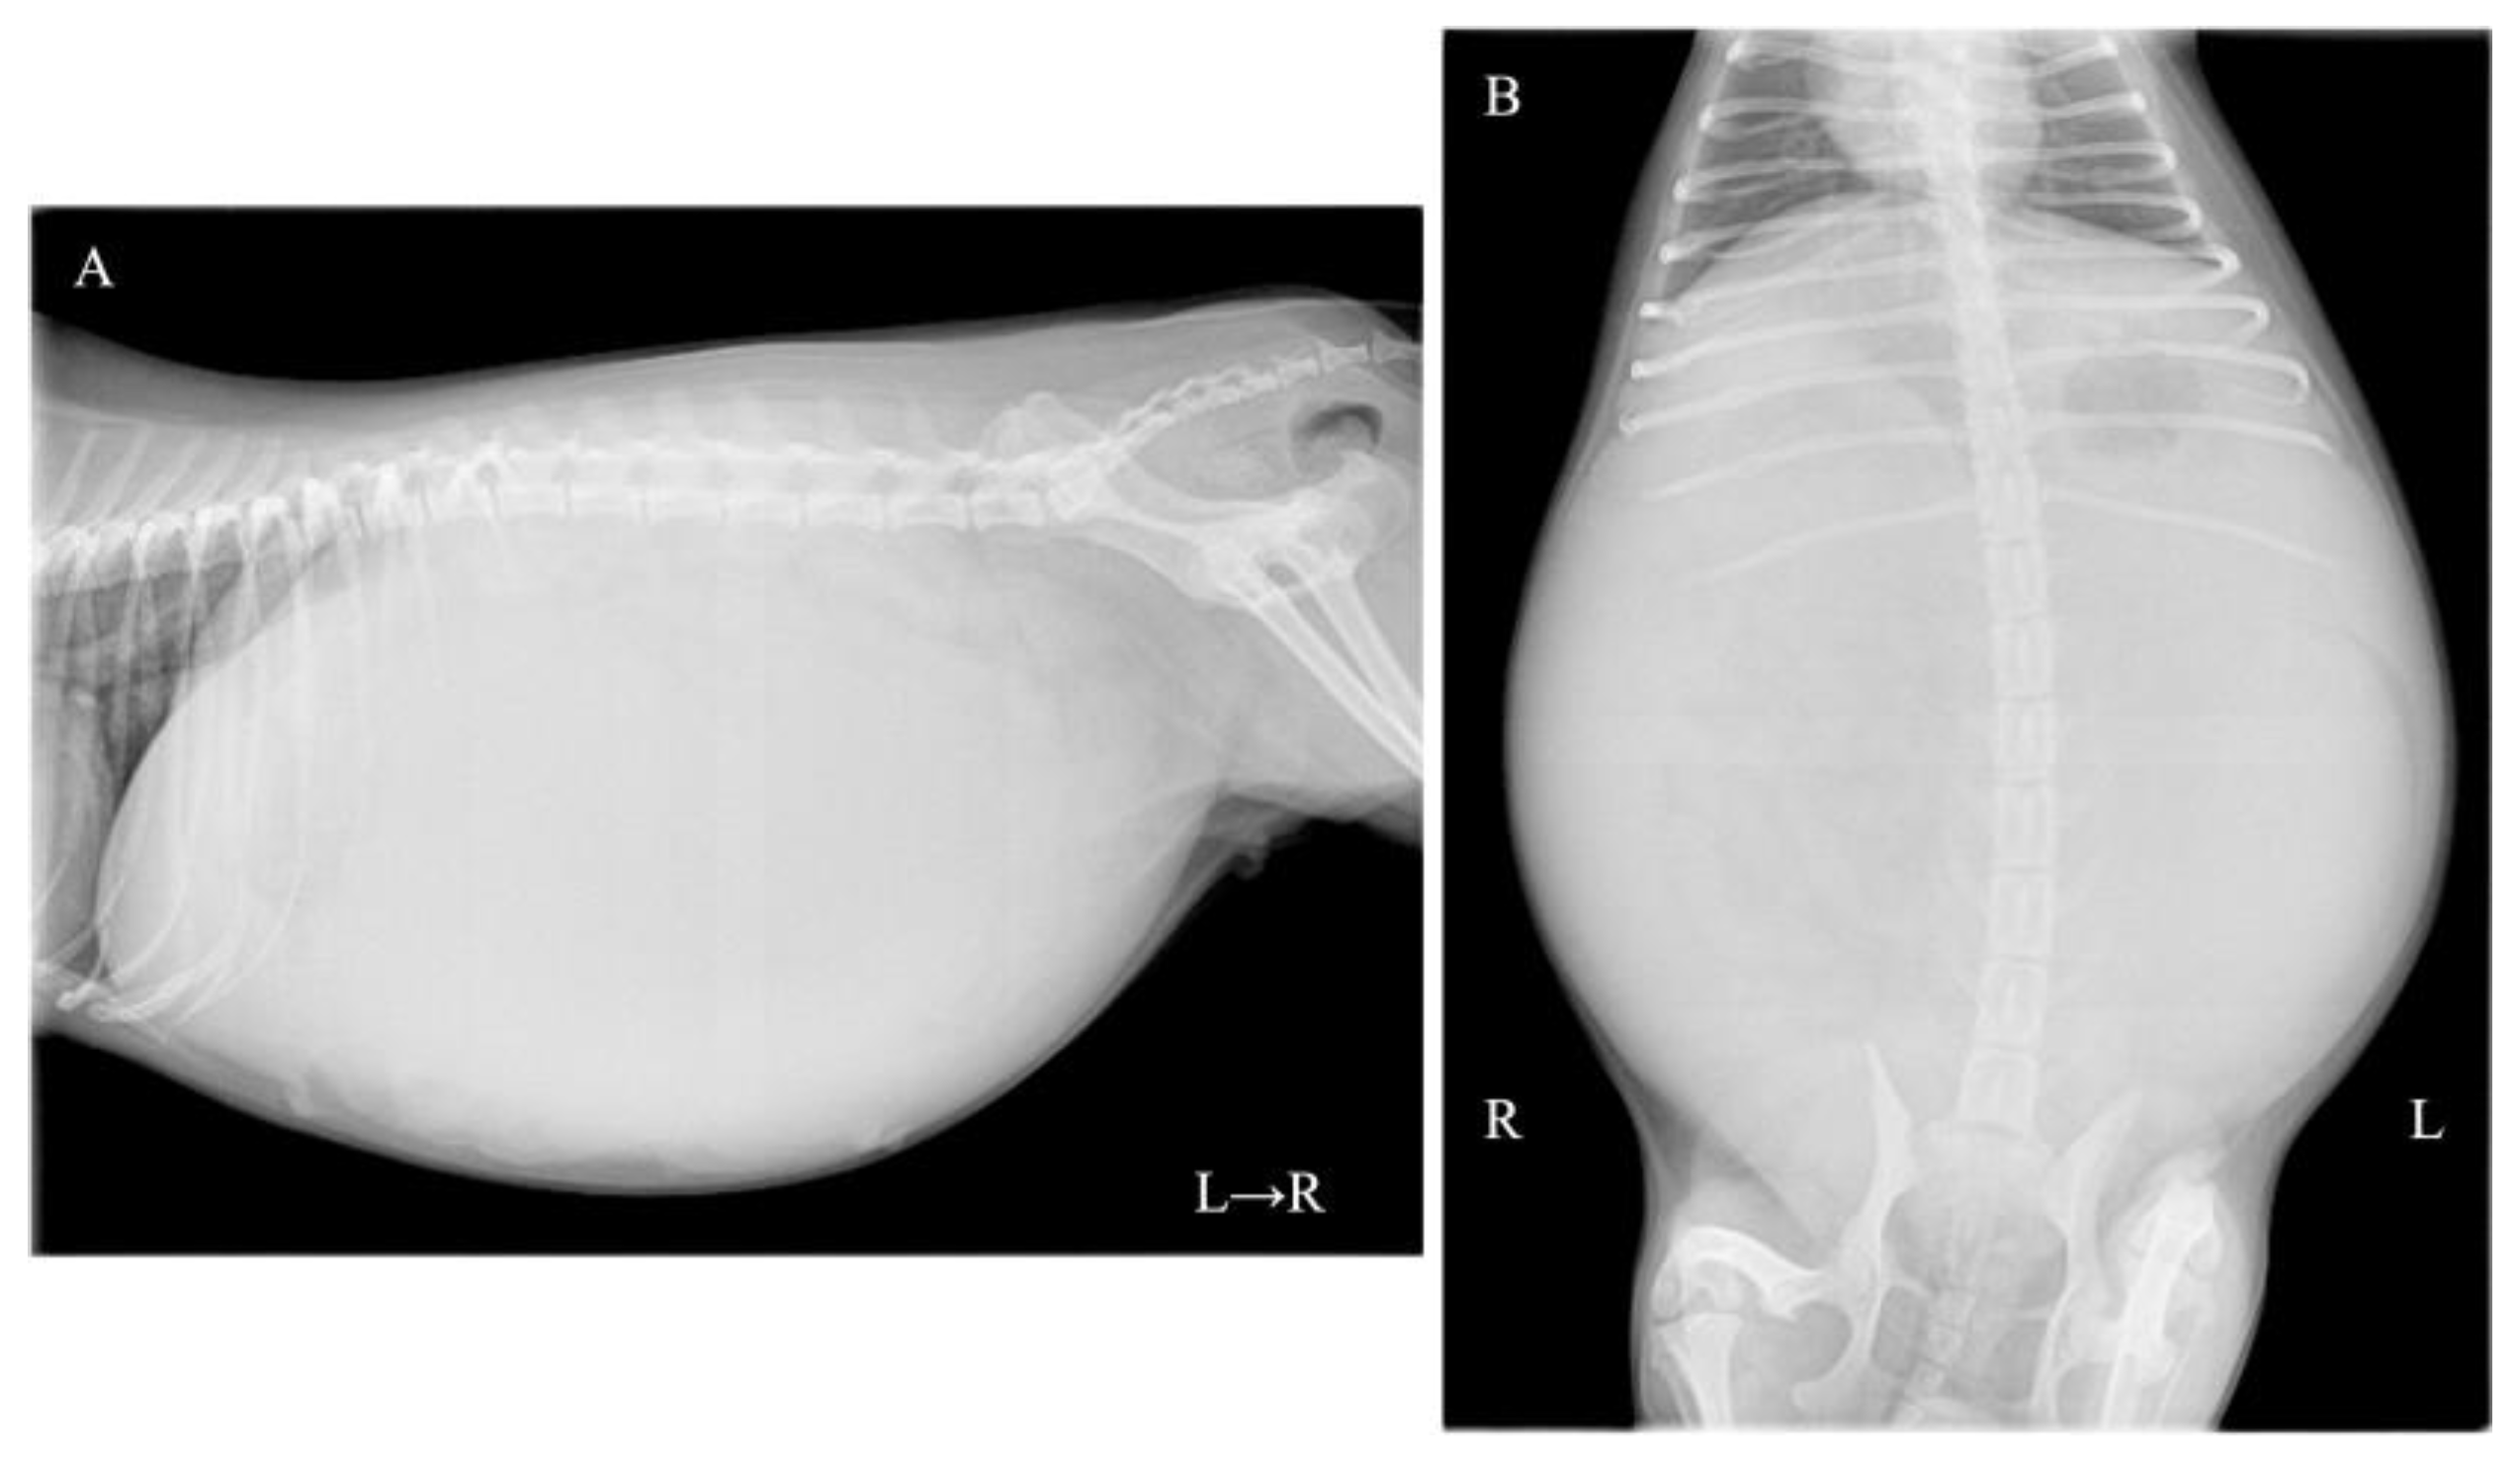

A one-year-and-two-month-old, intact female Pomeranian dog from a rescue organization was referred to the authors’ medical facility for the investigation of abdominal distension. The dog had been used for breeding and had a history of giving birth; however, specific details regarding the birth were unknown. According to the rescue organization, the dog had experienced one estrus before the operation. Clinically, at the time of presentation, the dog was in an anestrus stage. The dog had no history of abnormal estrous bleeding and had a normal estrous cycle. Upon the initial consultation, the patient showed no abnormality in its activity level, appetite, defecation, and urination, and there was no evidence of dyspnea due to abdominal distention. The dog weighed 3.9 kg with a body condition score of 3/5 and showed a severe abdominal distension but without any sign of pain or discomfort. Physical examination revealed a body temperature of 38.5 °C, with a heart rate of 144 beats per minute and a respiratory rate of 36 breaths per minute. The visible mucous membranes appeared pale pink, and no swelling or enlargement of the superficial lymph nodes was observed. Complete blood count (IDEXX ProCyte Dx; IDEXX Laboratories, Inc., Westbrook, ME, USA) revealed mild leukocytosis (22,800/μL; reference interval (RI) 2870–17,020/μL) and mild anemia (hematocrit: 30.0%; RI 30.3–52.3%). Serum biochemical analyses were performed using the (DRI-CHEM NX700; FUJIFILM Corporation, Tokyo, Japan), and the results (albumin; 2.7 g/dL, blood urea nitrogen; 11.7 mg/dL, alanine aminotransferase; 15 U/L, sodium; 139 mEq/L, potassium; 3.8 mEq/L, chlorine; 102 mEq/L) were within reference intervals. Thoracic radiography did not show any apparent abnormalities. Abdominal radiography revealed a left abdominal mass occupying the area from the last rib to the pelvis with displacement of the small intestine to the right, along with decreased contrast of intra-abdominal organs (Figure 1A,B). No other obvious abdominal abnormalities were noted. An abdominal ultrasound (ALOKA LISENDO880; Hitachi Ltd., Tokyo, Japan) detected a mass lesion extending throughout the left abdomen, with the mass located just ventral to the left kidney and in close contact. The left ovary and uterus were not identified around the left kidney. The mass exhibited heterogeneous echogenicity depending on the region, predominantly consisted of a homogeneous parenchymal area (Figure 2A), but partially contained a cystic area (Figure 2B). For the cystic area, anechoic regions were scattered within the cyst. Color Doppler examination revealed relatively poor vascularity in the parenchymal areas (Figure 2C) and abundant blood flow in the cystic areas (Figure 2D). A small amount of peritoneal effusion was observed around the bladder but was too small to collect for analysis. Echocardiography showed no obvious abnormalities in cardiac function. Based on these findings, a tentative diagnosis of an intra-abdominal mass near the left kidney suspected to originate from the female reproductive organ was made. Differential diagnoses included ovarian tumors (such as epithelial tumors, sex cord-stromal tumors, germ cell tumors, mesenchymal tumors) and uterine tumors (such as mesenchymal tumors, epithelial tumors).

Figure 1. Abdominal radiographs: (A) right lateral recumbency image and (B) ventrodorsal image revealing a mass in the left abdominal region with displacement of the small intestine to the right.